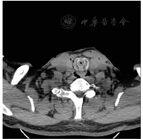

患者,男,51岁,1 d前无明显诱因出现右上腹疼痛不适,伴有发热,无畏寒,无胸闷、心悸,无恶心、呕吐,无头痛、头晕,无腹泻、黑便,无尿频、尿急、尿痛等症状,遂就诊于当地医院,查腹部B超示胆囊结石、胆囊炎。为求进一步治疗来院就诊,门诊拟"胆囊结石伴急性胆囊炎"收入病房。患者自发病以来,精神、饮食、睡眠欠佳,有声音嘶哑,有呼吸急促史,大小便正常,体质量较前无明显变化。患者既往有胸部外伤史,具体不详;否认糖尿病、高血压病史,否认肝炎、结核病史,否认输血史,否认食物、药物过敏史。诊断为胆囊结石伴急性胆囊炎,术前血气分析为低氧状态,拟于2016年6月20日在全身麻醉下行腹腔镜下胆囊切除术,麻醉师诱导后在直接喉镜下无法插入4.0号气管插管,并发现声门区肿胀,声门下区严重狭窄,黏膜易出血;给予喉罩下吸氧,患者二氧化碳分压>60 mmHg(1 mmHg=0.133 kPa)。请耳鼻咽喉科急诊下行气管切开,切口2、3气管软骨后见气管严重狭窄并有肿瘤样组织,取部分肿瘤样组织送病理检查,并强行入4.0号气管插管,改善患者通气,但患者的二氧化碳分压较大,给予扩大切口并放入6.0号气管插管,术后转重症监护病房。转重症监护病房后行颈胸部CT检查示:喉黏膜增厚,气管、右支气管内见环形高密度钙化影,上段气管见明显狭窄(见封四图1、图2),双侧肺不张。次日上午再次出现呼吸困难,发热,脉搏氧饱和度(SpO2)下降,立即给予甲泼尼龙静脉推注,利多卡因气道内滴入,氨茶碱泵入,并给予呼吸兴奋剂泵入,患者氧合情况逐渐好转,血氧饱和度最高达91%,于12∶00出现血压下降,立即予去甲肾上腺素0.11 μg/(kg·min)泵入,同时给予静脉补液,经治疗后生命体征不平稳,查体:体温(T)37 ℃,心率(P)72次/min,呼吸(R)27次/min,血压(BP)88/50 mmHg,血氧饱和度(SpO2)88%,气管导管在位,重度昏迷状态,患者家属放弃治疗,出院后不久死亡。术后病理示:黏膜下结缔组织增生伴淀粉样变性(见封四图3)。

LTBA在内窥镜下呈喉及气管内弥漫性肿胀,偶见黏膜下结节状团坎,不伴溃疡,常呈黄色、半透明石蜡状。LTBA影像学诊断主要靠CT。因CT能够显示病灶内部结构,喉气管支气管粉样变性由于蛋白质沉着可出现不同程度钙化,CT同时可分辨钙化与成骨性钙化不同,并且CT通过调动窗宽窗位可以清楚显示钙化,也是与喉部恶性肿瘤的鉴别之一。淀粉样变部位CT密度较高,一般高于肌肉密度,CT值40~60 Hu,可以帮助诊断,但在病变周围常伴有局部的慢性炎性反应。由于淀粉样物质呈块状、斑片状沉积在黏膜下,故CT上表现为增厚的室带等喉腔内组织、气道管壁增厚,气管黏膜面多凹凸不平,呈结节状、波浪状,管腔不规则狭窄。CT可清楚地了解气道内淀粉样变性为局限性还是弥漫性:局限性表现为管壁的局限性结节,管腔向心性狭窄;而弥漫性则为管壁的弥漫性围管性增厚。同时,CT三维重建还有助于了解病变范围并制订详细的手术方案。而常规喉部X线侧位片和正位片仅能提示喉部有病变,只对喉部淀粉样变性具有一定诊断价值[5]。